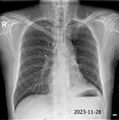

16. 2023/11/28 화,

1. X-ray 촬영